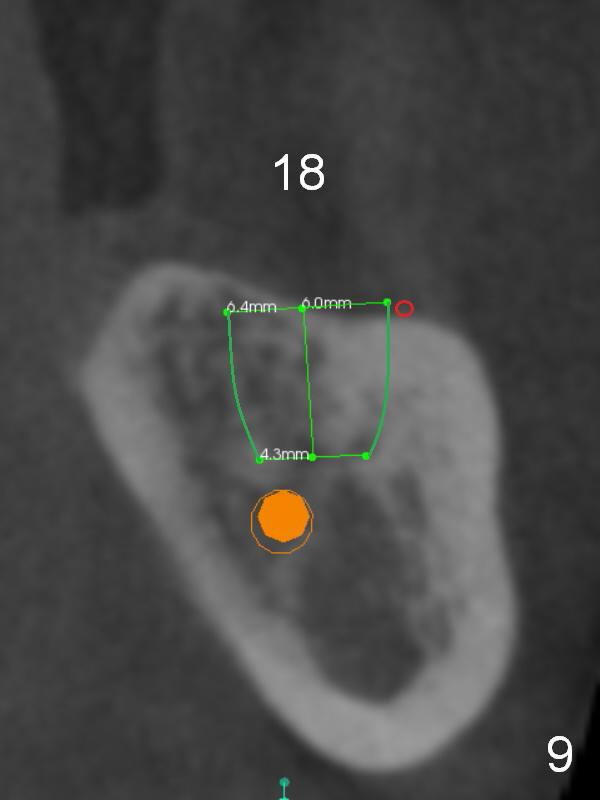

There is severe bone resorption around the distal root of the lower left 1st molar of the 56-year-old man (WG), while the loss of the 2nd molar is associated with limited bone height (Fig.1). A 5x14 mm implant will be placed at the mesial socket of #19 and 5.9 or 6.4x6 mm one is at the mesial site of #18 (Fig.7-9). Use a 2 mm pilot drill with 6 mm stopper from Sinus Master Kit (with extension) to initiate osteotomy at #18 immediately distal to the crown of #19, parallel to the long axis of the latter (Fig.2). After inserting a parallel pin at #18, extract the tooth #19 (Fig.3, antibiotic pending) and start osteotomy with a 2 mm pilot drill with 14 mm stopper (Fig.4). Insert the calibrated parallel pin at #19 (Fig.5) and measure the distance between the two parallel pins (approximately 10 mm, Fig.7). Sequential osteotomy and application of the Tatum taps (Fig.6 red rectangle) will push the septum distal (green arrow). As to #18 osteotomy, trephine, final and tap drills are to be used with control of the depth: 6 mm (Fig.7,9).